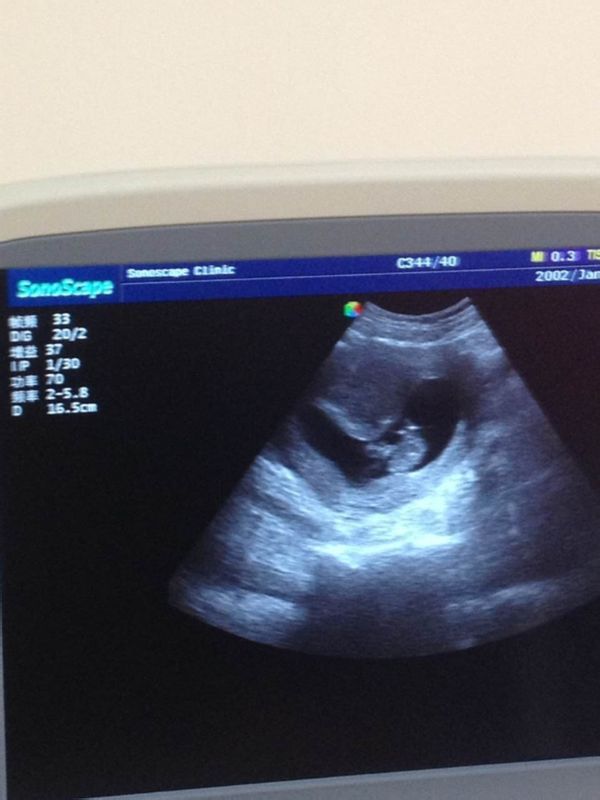

怀孕11周,b超显示膀胱欠充盈,后位子宫,子宫切面大小约为73*73mm,形态欠规则,轮廓清楚,实 质回声中等,光点细,分布均匀,宫内可见一大小约55*41*69mm妊嚢,其内可见胚胎组织和原始心搏,头臀长约42mm,请问高手,本胎是男孩还是女孩,谢谢!请速答 点击展开 189*****012_elu4 2015-03-23 22:59 为您推荐: 其他回答 你好,根据孕囊的大小不可能知道是男孩女孩的,只要是宝宝健康比什么都重要的 天使7737 2015-03-23 23:05 相关问题 膀胱充盈,子宫前位,宫休约4 6×3 5×4 3外形规则,肌壁切面回声均匀,宫腔内节育环距宫底约1 膀胱充盈度会影响子宫位置吗 怀孕45天,阴超回来 子宫增大 宫内见规则孕囊,囊内可见细小胚芽及微弱心搏,胚芽唱0 32,胎心率